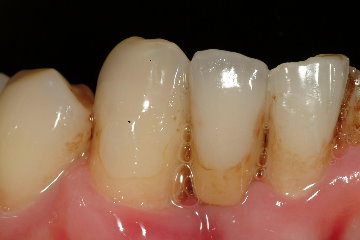

由於患者的下顎前牙區排列不整,因此與技師溝通牙齒之外形與排列必須與患者之原口內狀況相仿,而圖九及與圖十為技工室完成的植牙假牙模型

圖九 |